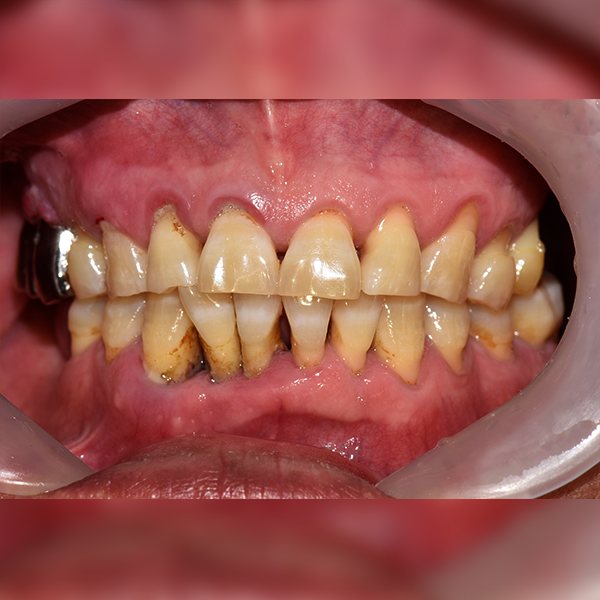

Тохиолдол.172 50-аад насны Ли*ган 2019-01-11 / 2019-07-24

Before Before

After After